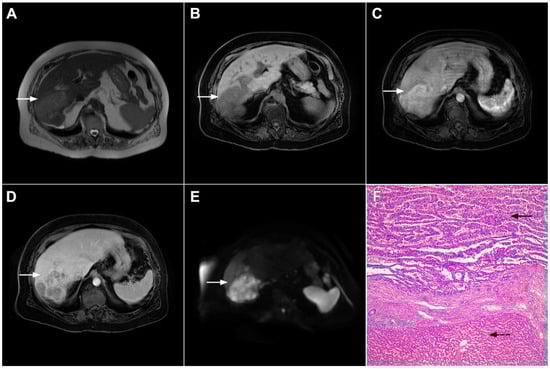

Target sign, consisting of diffusion restriction at the periphery of the lesion and low signal intensity in its central parts on high-b-value diffusion weighted imaging (DWI), could be considered to be a pathognomonic finding in mICC [16,17]. It can be attributed to the loose central fibrotic stroma with accompanying edema that is responsible for low signal intensity in DWI, while the periphery of the lesion is composed of densely packed viable tumor cells that cause diffusion restriction and dark rings on the apparent diffusion coefficient (ADC) map (Figure 3) [16].

Figure 3.

Mass-forming intrahepatic cholangiocarcinoma in the left liver lobe of a 76-year-old man. Axial T2-weighted FS image shows lobulated hetrogeneously hyperintense hepatic tumor (arrow) with perilesional biliary dilatation (A). Axial diffusion-weighted image (b = 800 s/mm2) shows target-like appearance (arrow) of the lesion that consists of a central darker area and a peripheral hyperintense area (B). Corresponding ADC map is shown on (C).

If hepatocyte-selective contrast media are used, mICC presents typically as hypointense lesions on the hepatobiliary phase due to the lack of functional hepatocytes with a sharp margin between the tumor and the background liver parenchyma [7]. Thus, tumor size as well as the presence of perilesional satellite nodules, could be more precisely evaluated in the hepatobiliary phase in comparison to the MRI with conventional extracellular contrast [18,19]. Additionally, the “cloud sign”, seen as a relatively high cloud-like signal intensity in the central part of the lesion surrounded by a hypointense peripheral rim, is considered characteristic of mICC (Figure 4) [19]. The appearance of mICC in the hepatobiliary phase may be used as a prognostic factor since it correlates well with the content of intralesional fibrous stroma [20]. Namely, if cloud sign is seen it indicates a large amount of fibrous stroma in the central parts of the tumor, which is frequently associated with poor prognosis [20]. Additional imaging features, which are shown to be prognostic factors and can be assessed in the hepatobiliary phase, include capsule penetration and hepatic vein obstruction, as was demonstrated in the study by Kim S et al. [21].

Figure 4.

Mass-forming intrahepatic cholangiocarcinoma in a 68-year-old woman. Axial T1-weighted image after gadoxetic acid administration obtained in arterial phase (A) shows peripherally enhancing lesion (arrow). Portal venous phase in the same patient (B) shows progressive centripetal enhancement of the lesion (arrow) with cloud-like appearance in the hepatobiliary phase (C) consisting of an area of central enhancement and a thin, peripheral, hypointense rim.